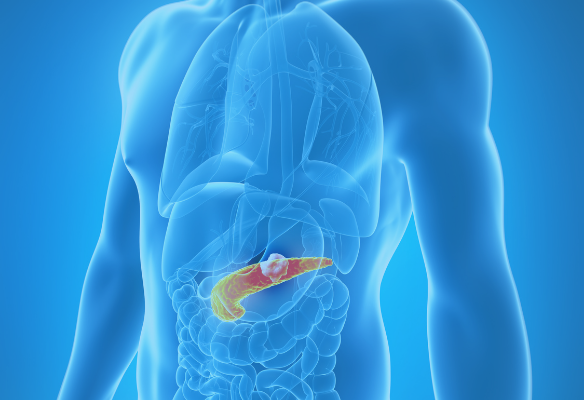

NFCR-funded researchers are all, in some way, using cancer genomics, but there are still certain cancer types that are most impacted by their projects. Specifics about those projects – as well as the cancer diagnoses – are outlined on the “Cancer Types” pages below.